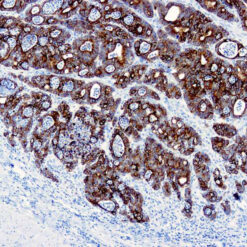

Synaptophysin (SYP02)

This antibody isspecific to a 38 kDa protein. Synaptophysin is an glycoprotein occurring in presynaptic vesicles of neurons in the brain, spinal cord, retina, vesicles of adrenal medulla and in neuromuscular junctions. This antibody reacts with neuroendocrine neoplasms of neural as well as epithelial types.

| Clone | SYP02 |

| Cellular Localization | Cytoplasmic |

| Positive Control Tissue | Pancreas |